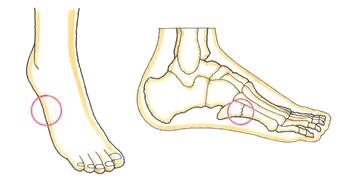

足小指の根元にある中足骨のイラストです。Bのほうが足先に近いです。

Aの部分が下駄骨折、Bがジョーンズ骨折です。

骨折部位は1センチメートルほどしか違いませんが、治療法や予後は異なってきます。